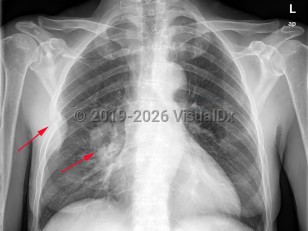

Lung cancer

Greater than 95% of lung cancers can be categorized as either small cell lung cancer (SCLC) or non-small cell lung cancer (NSCLC), with adenocarcinoma and squamous cell carcinoma being the most common NSCLC. Carcinoid tumors and mesothelioma may also arise in the lung but are less common. The lungs are also a common site of metastatic cancer.